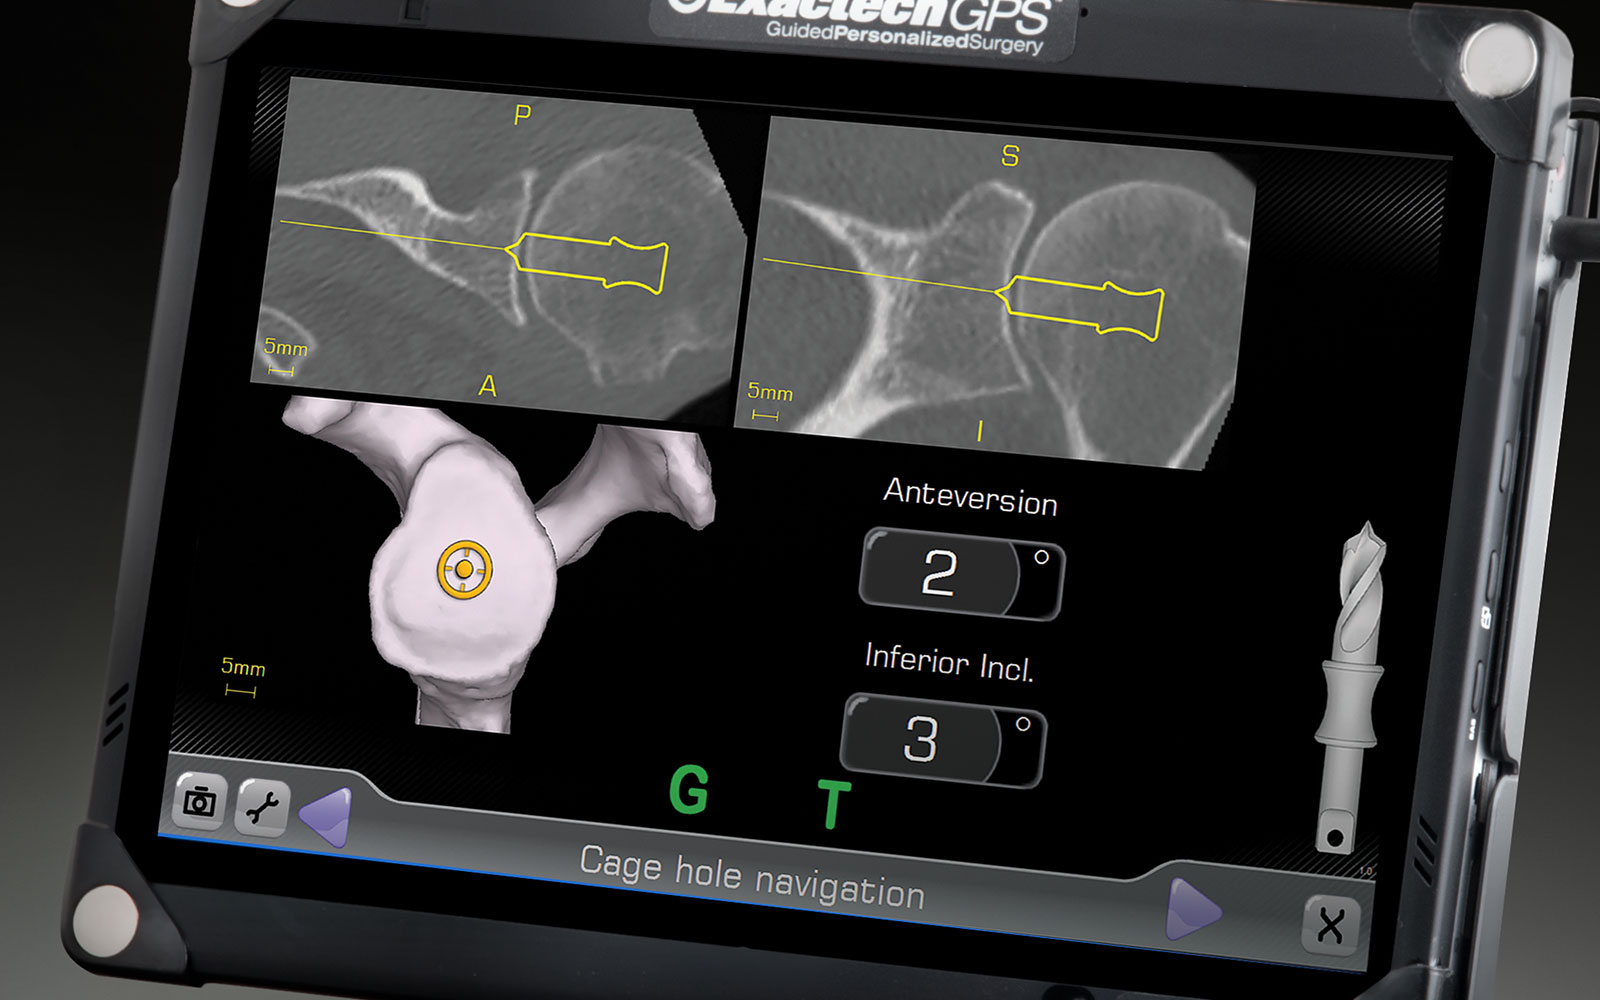

CT-Based Intraoperative Navigation for Glenoid Placement in TSA

Moby Parsons, MD